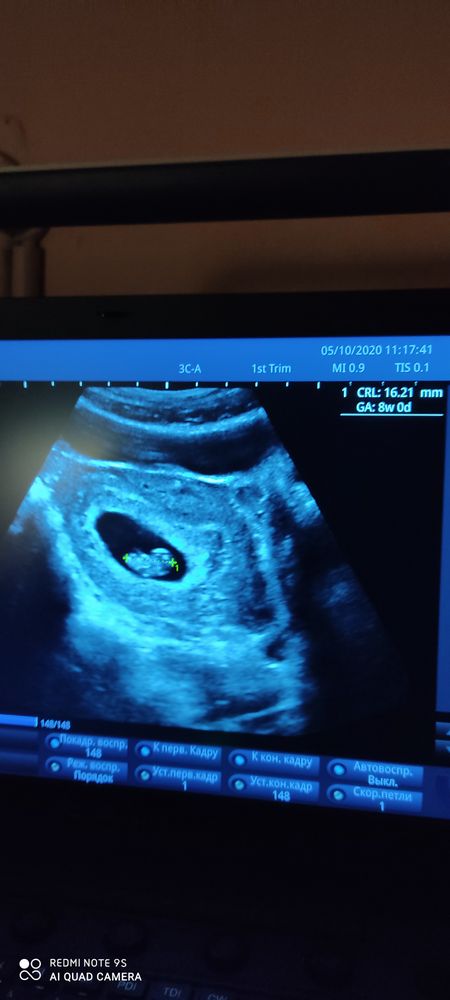

Была на УЗИ. 8+1 по мес.

УЗИ, КТГ, доплерДелала УЗИ при ЖК. Аппарат у них появился новый, но врач сказала сразу, что ещё не разобралась как ним пользоваться. На новом аппарате соответствует сроку 8+0, на старом 8+3. Говорит ❤️ есть и

Эмбрион жирненький. Вся информация поверхностная. Зная ещё профпригодность, ничего не спрашивала. Сегодня записана к хорошему врачу, переделаю УЗИ, сравню информацию. Спрошу обо всем тогда.

05.10.2020